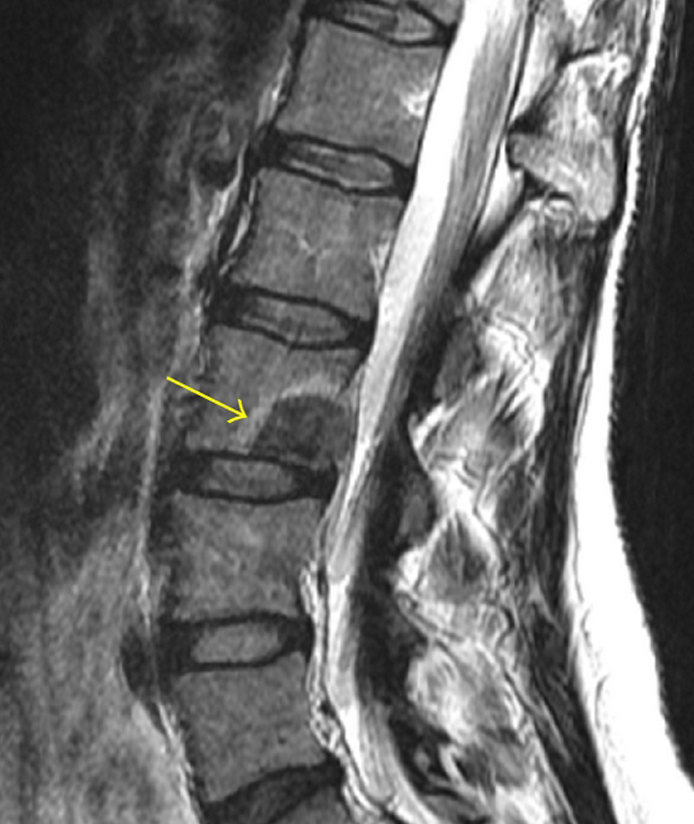

An image of an MRI showing a metastatic tumor in a patient's spine.

An MRI shows a metastatic tumor (yellow arrow) in a patient's spine.

Credit: Int J Surg Oncol November 2011. doi: 10.1155/2011/769753. CC BY 3.0.